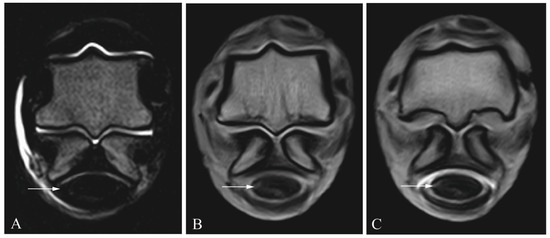

2.3. Diagnostic Imaging

2.4. Image Analysis